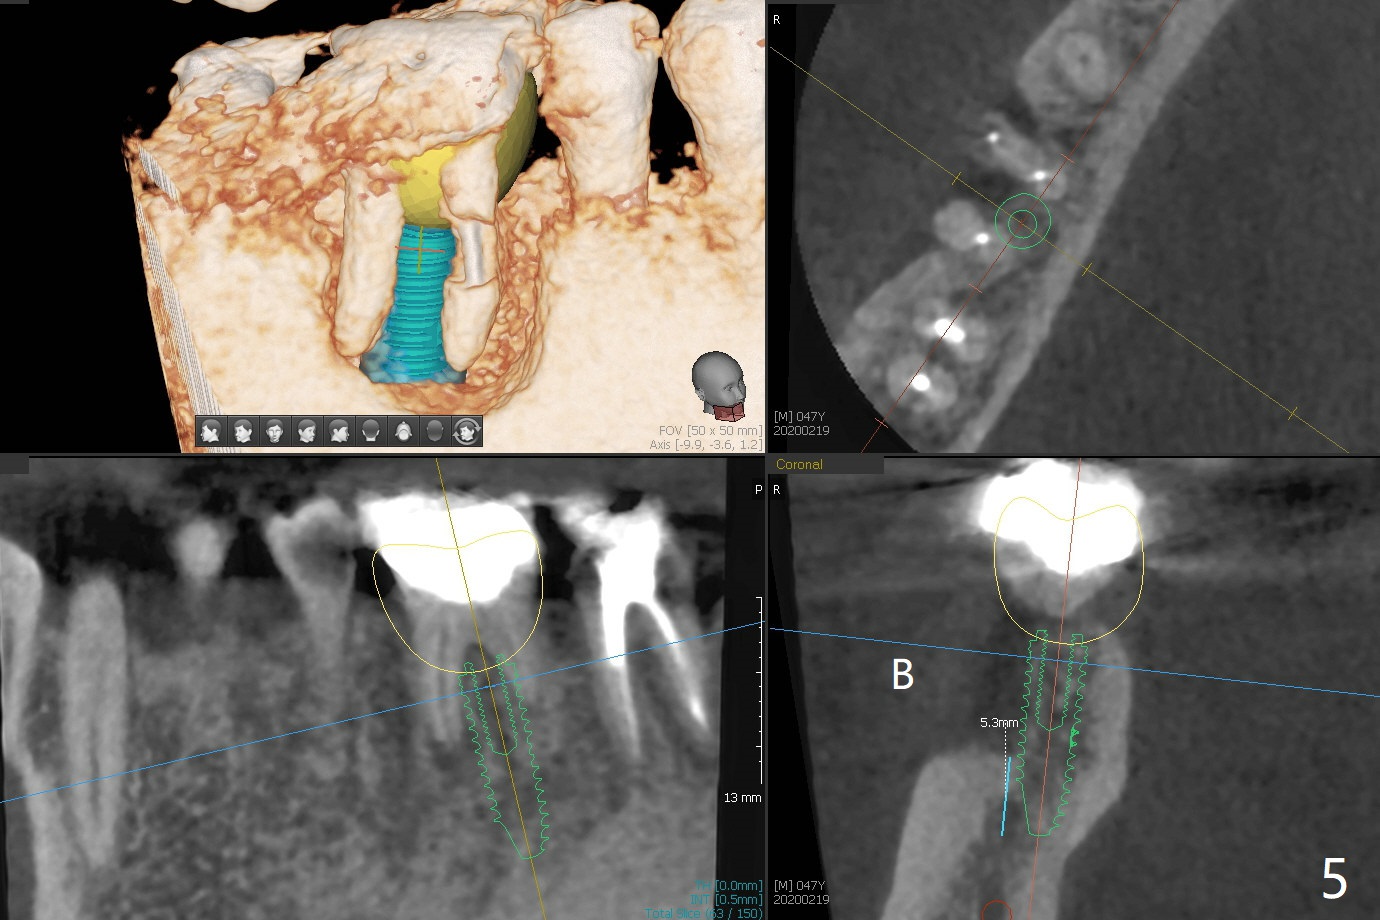

A 47-year-old man has poor dentition. The tooth #31 needs RCT, while #30 has severe PARL, especially mesial (Fig.1 M). The buccal roots are exposed (Fig.2). Between the exposed roots is the septal gingiva, which will be saved for buccal soft tissue repair (Fig.3 *). The septal gingiva will keep in place (not to be transferred) so that the recession will disappear by epithelial regrowth from the nearby gingiva (Fig.3' arrows) over the bone graft and PRF. The provisional should be fabricated to cover the soft tissue defect (Fig.3'' yellow area). In fact the mesial root fractures (Fig.4 ^), as related to the severe bony defect. There seems to be enough lingual bone to hold a 4x13 mm implant (Fig.5 green). Sticky bone (Fig.6 red circles) and PRF (blue) are to be used to repair the hard and soft tissue defects following an immediate provisional (Fig.5,6 yellow outline). Extra layer of acrylic (Fig.6 orange) will be used to cover the PRF buccally. The base of the buccal plate is thick (Fig.6 *); mesial portion appears to be denser (Fig.7 black *) than the distal one (white *). Decortication will be done if hemorrhage is insufficient. Fig.8 is a coronal section of the socket (B: buccal). Extraction (Fig.9 black area) will most likely result in a knife edge ridge. Extraction with bone graft may not fare better, as it is easy to lose the graft considering missing buccal hard and soft tissues.